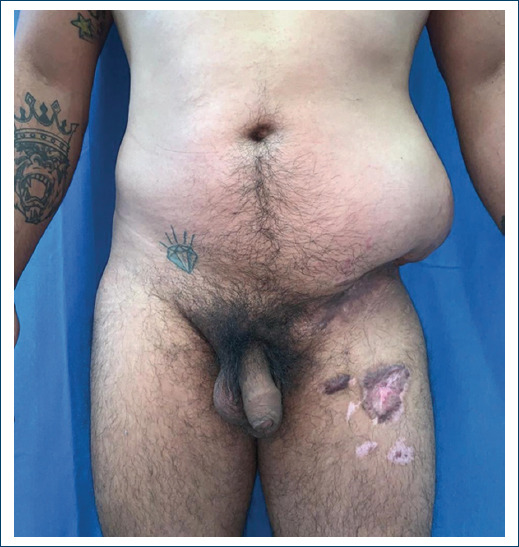

On physical examination, patient was found with abdominal asymmetry due to increased volume of the flank and left iliac surface, approximately 30x15x4cm, with hyperchromic coloration, skin with telangiectasias, skin and fat atrophy, localized hyperthermia, Intestinal peristalsis is palpable on the abdominal flank, it is not possible to delimit all the edges of the defect with palpation. A bone fragment corresponding to the anterosuperior iliac crest rotated lateral, anterior and caudal is palpated and above it, the hernia. There were no alterations in gait or sensory alterations in the area (Fig. 1). Computerized axial tomography shows (Fig. 2) the hernial sac containing the sigmoid colon and small bowel loops, the fracture of the anterior superior iliac crest, consolidated in an abnormal position, disinserted of the major and minor oblique muscles and retraction towards cephalic and posterior.

In the immediate postoperative period, the reduction (Fig. 5) and containment of the hernia was evident, the patient continued walking without difficulty or pain and was discharged having adequate pain control with oral medications. He continues with follow-up by external consultation 48 hours after the intervention. The drain is removed one week after discharge, once it has output of less than 30 ml/day and serous characteristics, the patient is kept without physical exertion for 6 months to avoid recurrence.